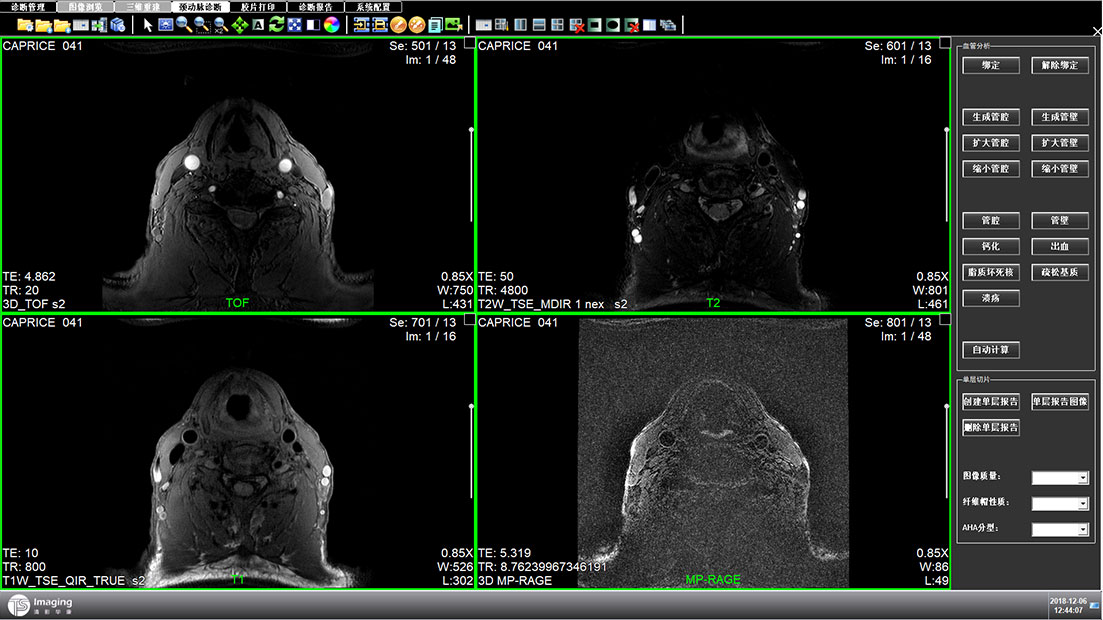

頸動脈診斷頁面

頸動脈診斷頁面整體布局和三維重建比較相似,最大的區(qū)別是右側(cè)的操作區(qū)域,血管分析都為按鍵操作,通過間隔的大小分成三部分。單層切片除了按鍵還有下拉菜單的操作。

頸動脈診斷原型